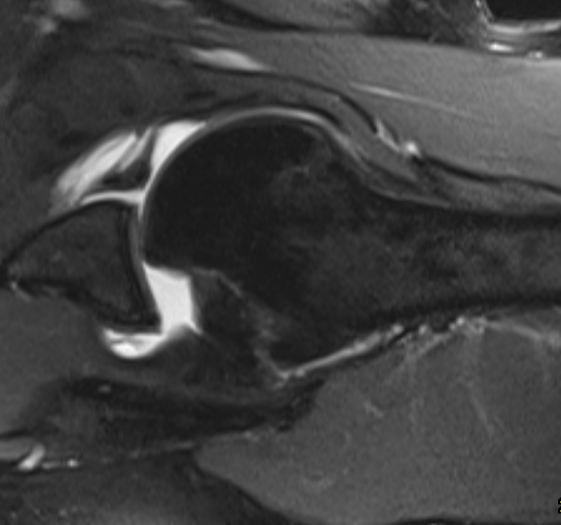

Hill Sachs defect and Bankart lesion